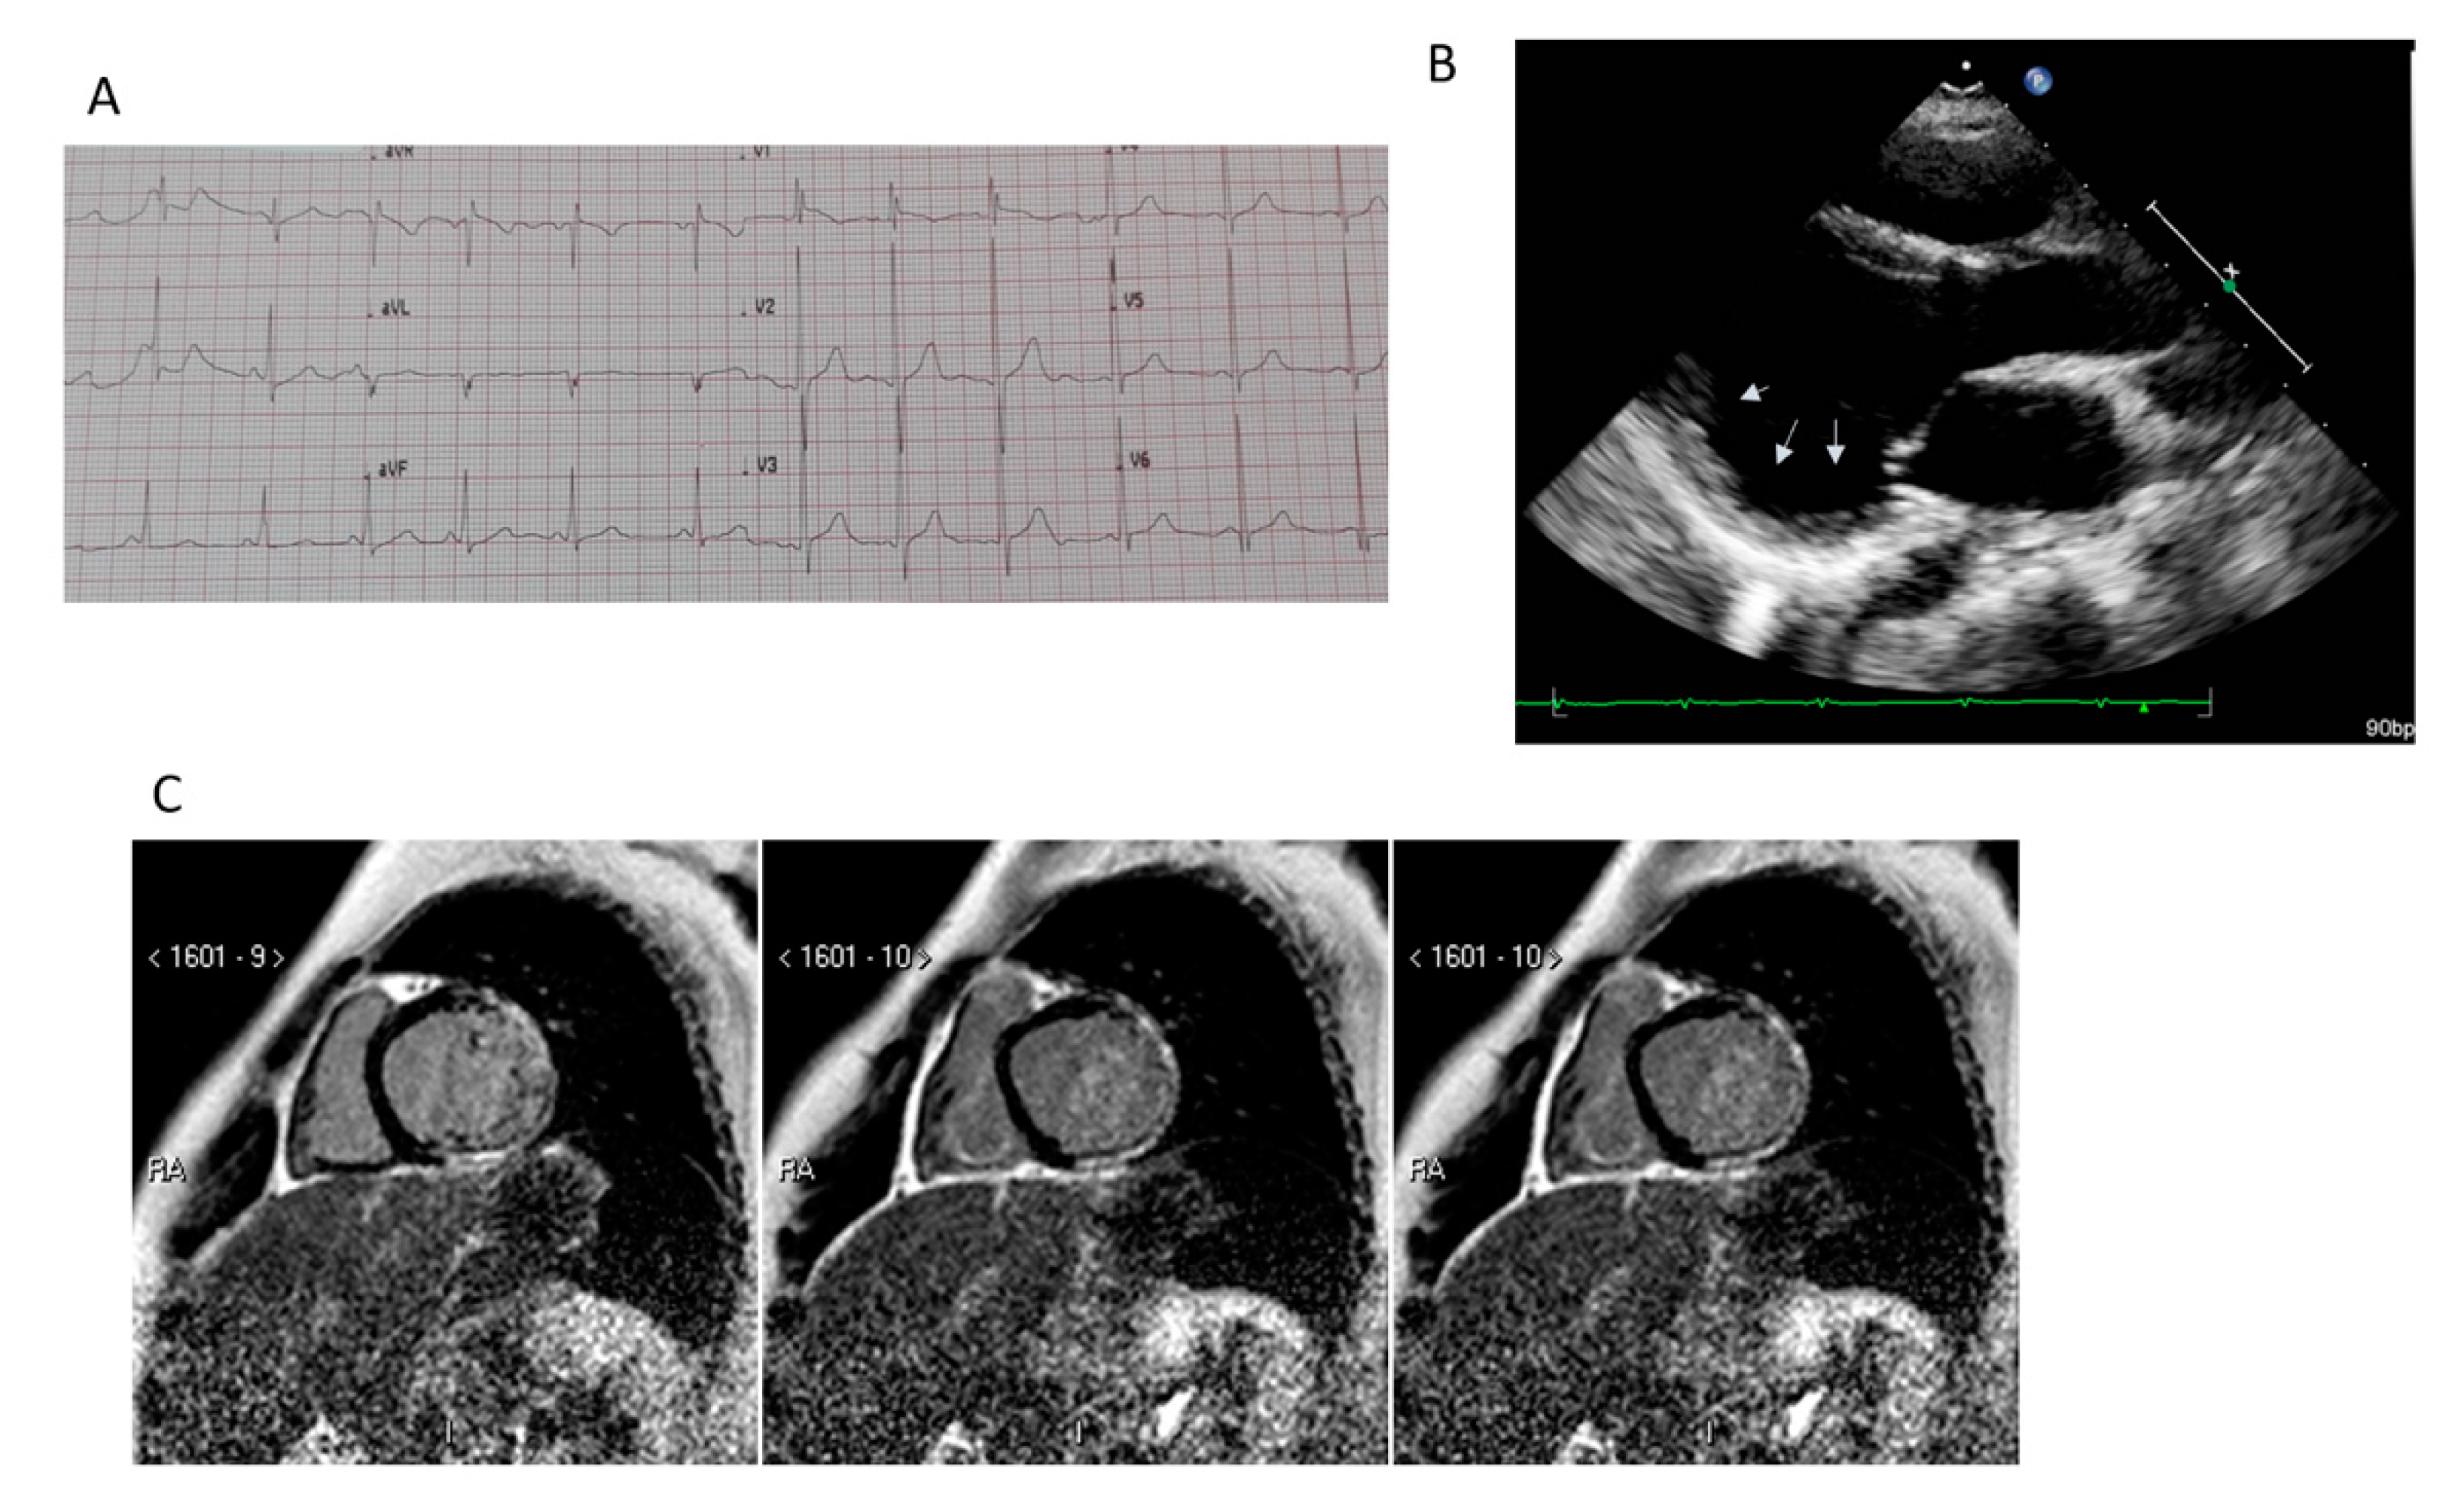

5.1. Transthoracic Echocardiography

8.1. Electrophysiologic Characteristics

8.2. CRT and Implantable Cardioverter Defibrillator